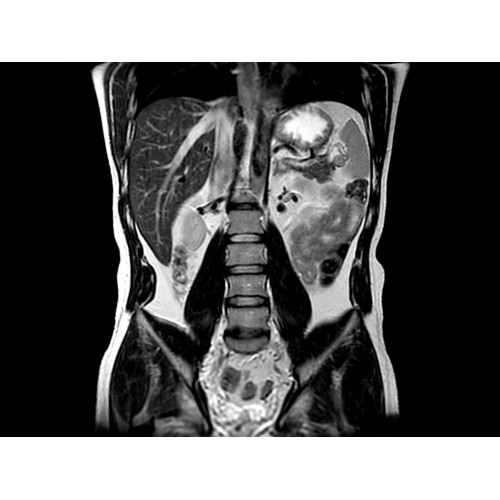

• Широкое поле зрения — поле зрения шириной 50 см позволяет охватывать крупные анатомические области за меньшее число сканов.

• Визуализация всего позвоночника слиянием двух участков — получить изображение всего позвоночника можно намного быстрее.

Помимо перечисленных возможностей, системы с широкими туннелями открывают дополнительные пути для диагностики и терапии. Расширение возможностей позиционирования пациента и доступа к нему позволяет использовать новые интервенционные и хирургические процедуры.